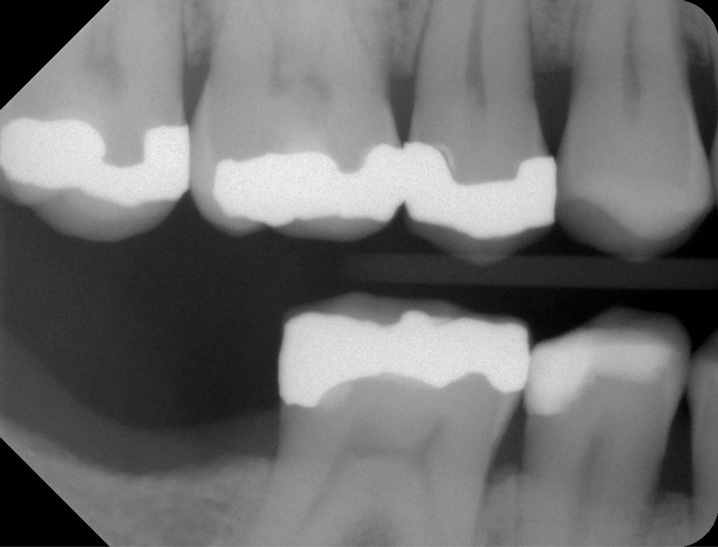

Fig 5. Patient No. 2 had an extraction of tooth No. 31 in 2009. Six years later, as shown, tooth No. 2 was extruded and needed to be removed due to caries.

Figure 5

If a patient chooses not to replace a missing second molar but desires to preclude over-eruption of an opposing molar, a preventive restoration may be fabricated. Examples of such a restoration may include bonding to an adjacent tooth, a metal splint bonded to adjacent teeth, a removable prosthesis, an extended prosthetic length of arch with a cantilever, or the use of a nightguard. This could prevent molar hyper-eruption, which may predispose an individual to plaque retention that could cause caries or periodontitis (Figure 5).40 Potential loss of interocclusal space also must be addressed with patients, because extraction of a second molar can result in migration of an unopposed tooth, which may complicate the replacement of the antagonist (Figure 6). Importantly, a super-erupted tooth may need to be significantly reduced before fabricating an opposing implant prosthesis, or an extruded tooth may need to be devitalized, crown-lengthened, or intruded to provide proper interocclusal space for a restoration.